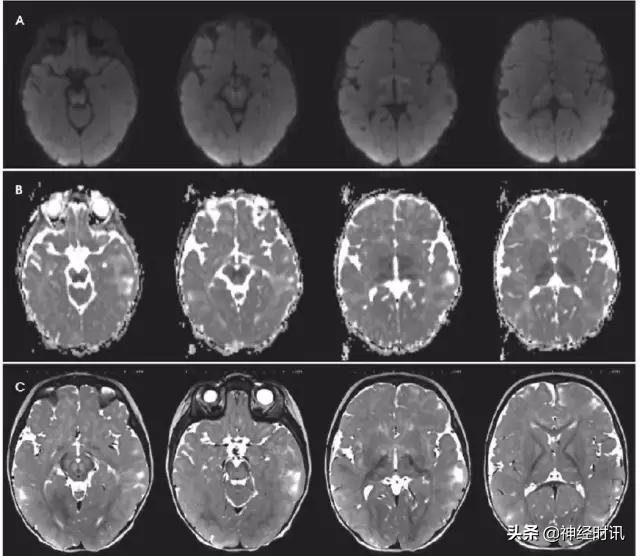

图6 一例48岁男性,近期2次左侧PCA分布区梗死,伴神经功能缺损加重,新发认知功能障碍和意识障碍。最终诊断为MELAS,FLAIR显示左侧后顶颞针叶非血管性分布的皮层水肿(A:FLAIR),同时伴弥散受限和弥散增加(B:DWI;C:ADC)。

图7 一例31岁男性,有*洛因海**和*卡因可**滥用史,出现无脉性电活动心搏骤停。MRI显示双侧顶枕叶和额叶、双侧丘脑弥漫性弥散受限(A:DWI,B:ADC)、T2-FLAIR高信号(C:FLAIR),符合全脑缺氧性损伤。

图8 一例62岁女性,复视3个月,听力丧失数天,因眩晕、恶心、呕吐、眼震和厌食来诊。她被诊断为营养缺乏导致的Wernicke病,硫胺素水平为35 nmol/L (正常70–180)。MRI显示四叠体板、中脑导水管周围灰质、下丘脑和双侧上丘FLAIR高信号和各种不同程度的弥散(A:DWI,B:ADC)。